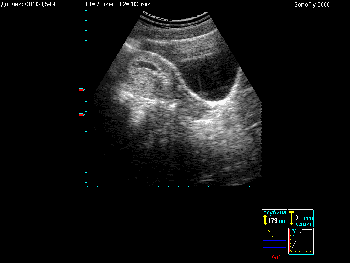

Примеры того, как выглядит экран при различных режимах сканирования можно увидеть в Таблице 4.

Таблица 4. Общий вид экрана в различных режимах сканирования.

Вид экрана Режим сканирования

Режим сканирования B Режим В